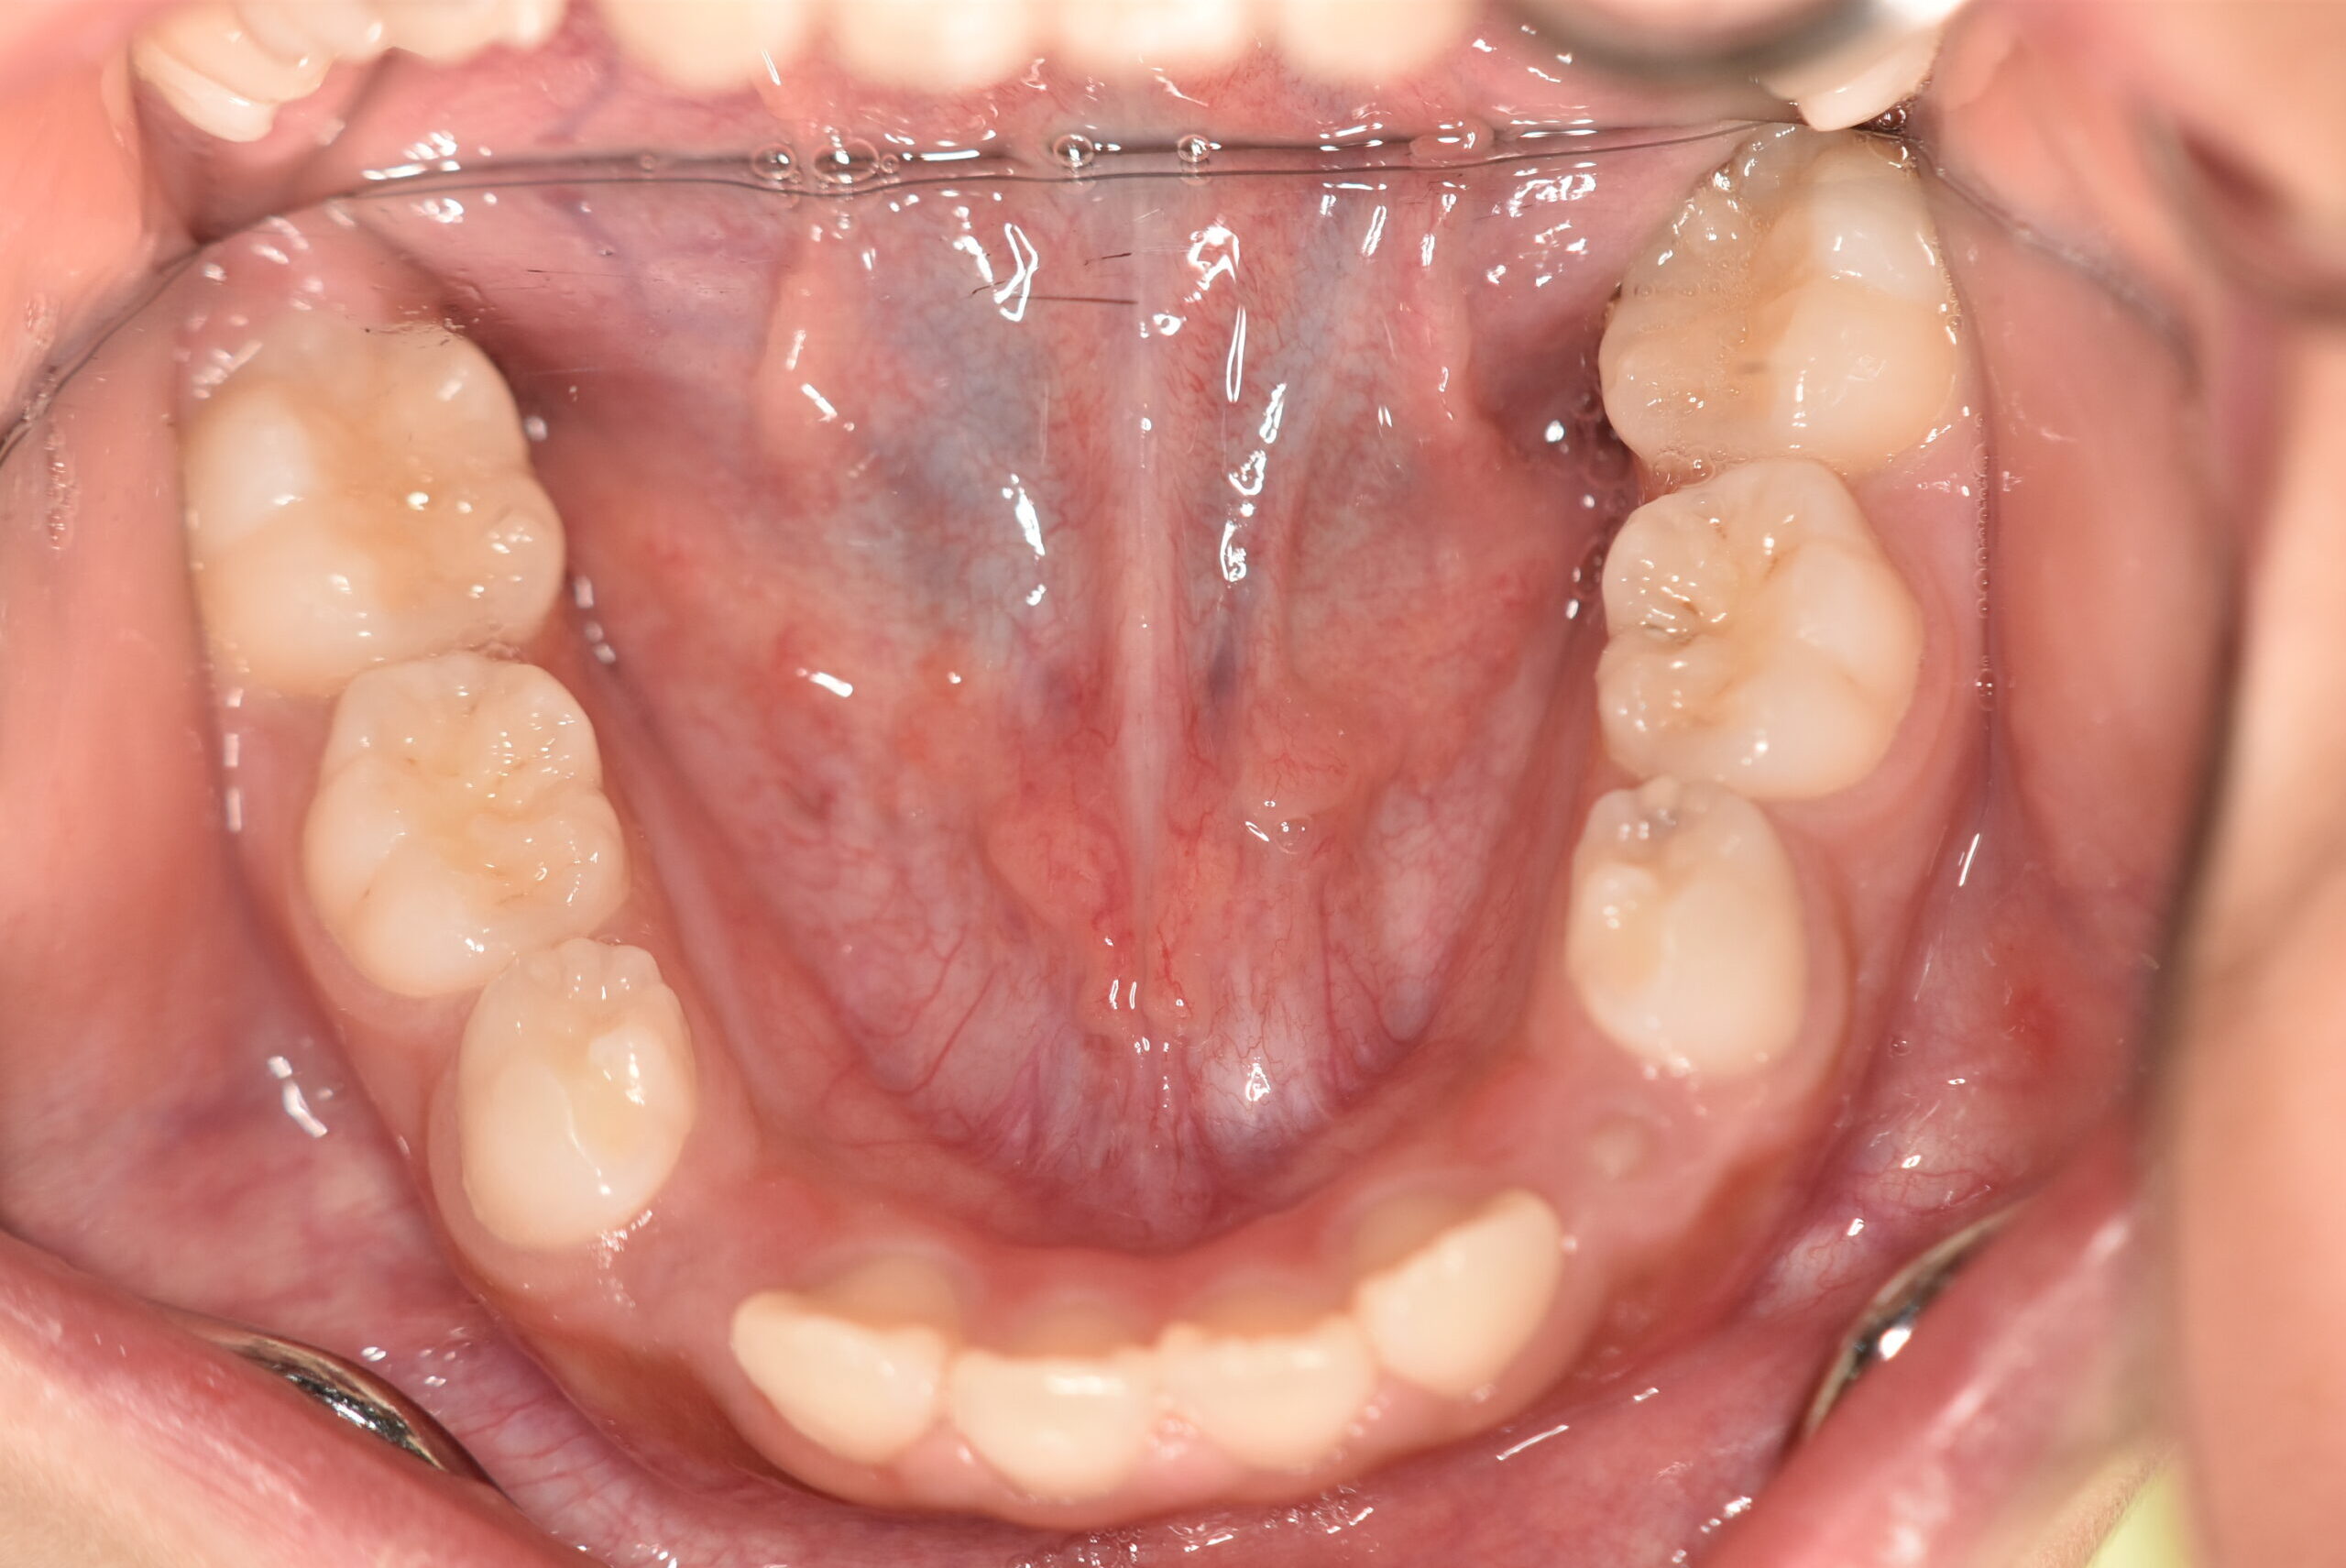

初診時

症例 症例 症例 症例

年齢

9歳 性 別 女性

治療内容の詳細 初診時9歳の女児で、歯のがたつきを気にされ来院されました。

検査の結果、前歯部叢生を伴うアングルⅠ級不正咬合と診断しました。

治療としてはマウスピース矯正(インビザラインファースト)で配列を行い、上下顎の側方拡大と萌出スペースを確保しました。

治療期間は、7ヶ月でした。

今後、側方歯生え変わりまで経過観察を行います。